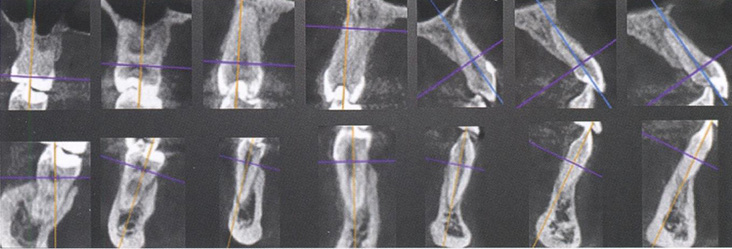

Непосредственно на компьютерных томограммах срезы каждого зуба выглядят следующим образом (рис. 80).

Кросс-секции зубов верхней и нижней челюсти справа на компьютерных томограммах в окне мультипланарной реконструкции

Рис. 80. Кросс-секции зубов верхней и нижней челюсти справа на компьютерных томограммах в окне мультипланарной реконструкции